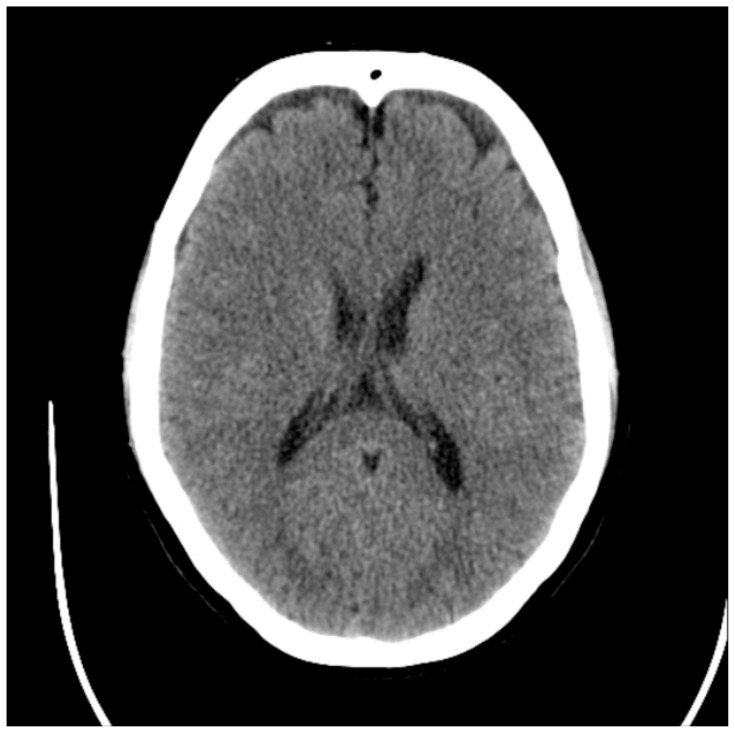

| #10 | Non-contrast CT Head |

Computed Tomography Head

Cuete, D. Normal CT brain. In: Radiopaedia. Published July 7, 2013. Accessed November 20, 2021. At: https://radiopaedia.org/cases/23768?lang=us.

Case Description & Diagnosis (short synopsis): This case involves a middle-aged male who experiences syncope secondary to subarachnoid hemorrhage. History and physical exams are significant for headache with maximum intensity at the onset with ongoing neck pain and stiffness. Unfortunately, the patient presents over 6 hours after onset, and the CT head is unremarkable, forcing the learner to obtain a lumbar puncture to ultimately make the diagnosis.

How the scene unfolds: The learner should start by placing the patient on cardiac and pulse oximetry monitoring, revealing hypertension with normal heart rate, respiratory rate, and oxygen saturation. The learner should then obtain additional history. If asked more questions about his headache, the patient says he has never had a headache like this. He says it was the worst headache of his life but is somewhat better now. If asked about timing, the patient says the incident happened about seven hours ago (he presented four hours after the event and was in the waiting room for three hours). If asked further review of systems questions, the patient denies hematemesis or melena, tongue biting or urinary incontinence, confusion after falling, or a history of seizures. In addition, he denies any recent medication changes. The learner should then perform a physical exam that reveals an uncomfortable but non-toxic male with normal orientation and cranial nerves exam but nuchal rigidity and reduced neck flexion. The learner should then order diagnostic testing to include at least POC glucose, CBC, CMP, ECG, and CT head. Other optional testing may include troponin, d-dimer, bedside cardiac ultrasound, and vital orthostatic signs. CT head should be interpreted as negative for the acute intracranial process, but the learner should recognize that they cannot adequately rule out SAH based on a negative CT head at over 6 hours after symptom onset, and LP should be performed.

○ SAH appears as blood in the subarachnoid spaces (ventricles, cisterns, sulci) on CT head imaging

○ CT Head without contrast sensitivity for SAH depends on the concentration of hemoglobin which becomes hemosiderin over time

■ ACEP Clinical Policy: “Use a normal non-contrast head computed tomography* performed within 6 hours of symptom onset in an emergency department headache patient with a normal neurologic examination to rule out nontraumatic subarachnoid hemorrhage.”4